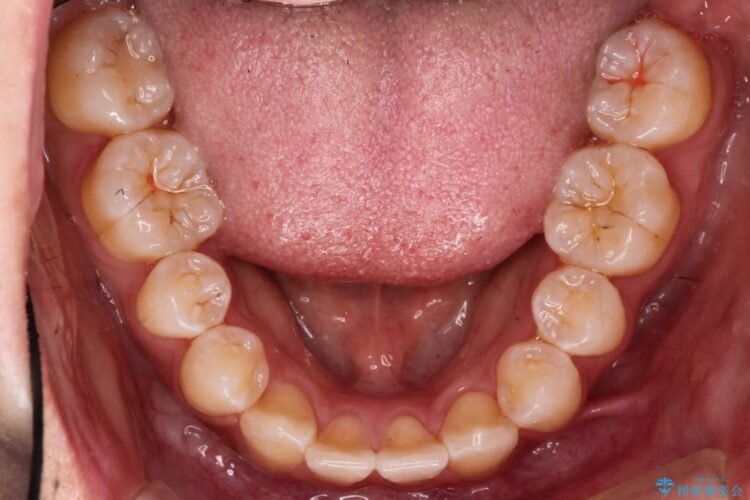

今回は乳歯を抜歯することで、上下の歯の本数がそろい、正中が一致し、バランスの良いかみ合わせにすることができました。患者様にも大変満足していただける仕上がりとなりました。